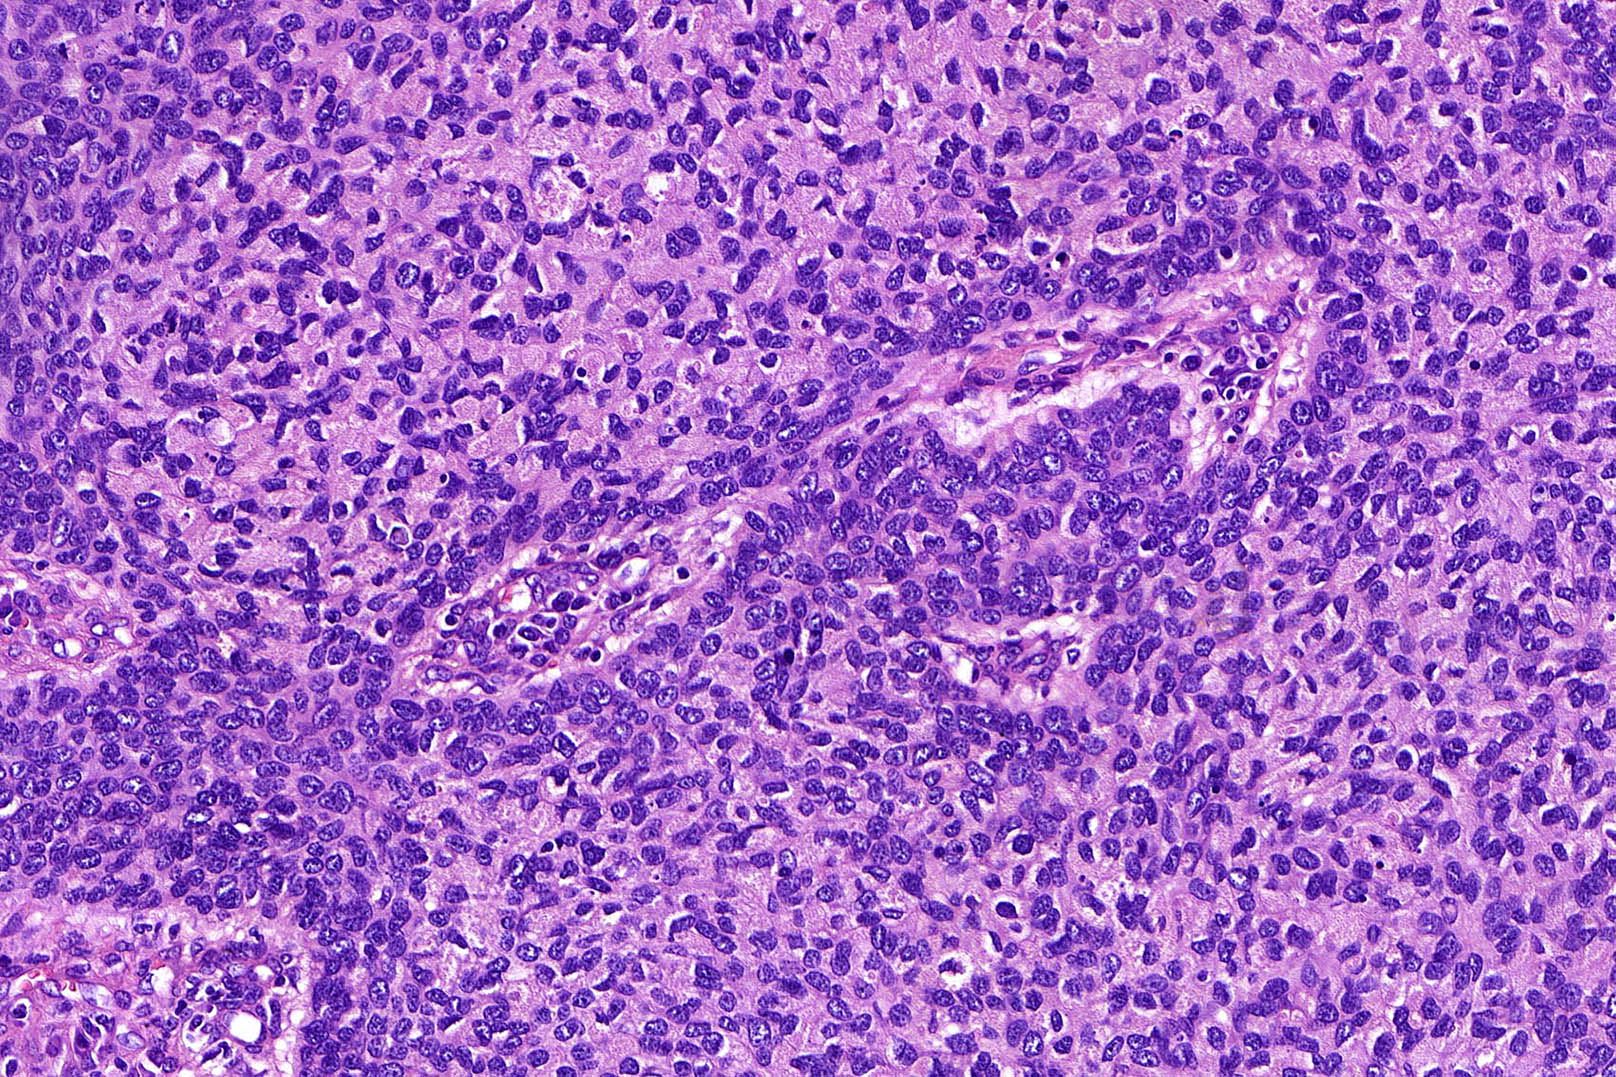

Common variants (Calonje: McKee's Pathology of the Skin, 5th Edition, 2019)

- Nodular and nodulocystic BCC

- Relatively circumscribed mass

- Epidermal or follicular attachment variably present

- Large basaloid lobules with peripheral nuclear palisade

- Lobules may be solid or show central cyst formation due to excessive mucin production

- Fibromyxoid stroma

- Cleft formation between tumor lobules and stroma

- Pleomorphism is generally mild

- Variable mitotic activity and apoptosis

- Sometimes necrosis en masse

Microscopic (histologic) images

Contributed by Antonina Kalmykova, M.D., Phillip H. McKee, M.D., Sate Hamza, M.D., Eduardo Calonje, M.D.,

Wayne Grayson, M.B.Ch.B., Ph.D., James Sampson, M.B.B.S., M.Sc. and Assia Bassarova, M.D., Ph.D.